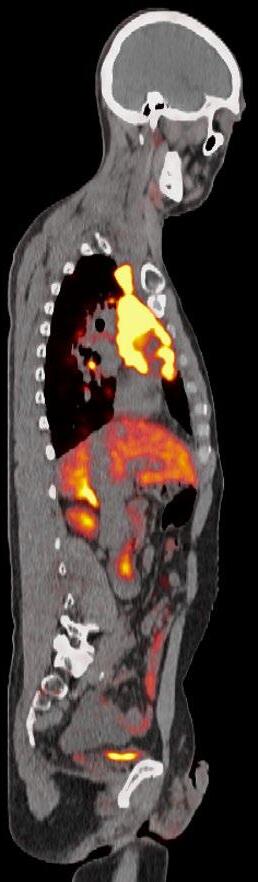

Maximum intensity projection (MIPs) images from DOTATATE PET/CTs before and after treatment with peptide receptor radionuclide therapy (PRRT). Baseline DOTATATE PET demonstrates numerous sites of markedly avid positive disease indicating the patient is a candidate for PRRT.  Post-treatment imaging demonstrates improvement in the extent of disease, although extensive residual disease.

Pascual's care team included medical oncologist Claire Mulvey, MD, and radiologist Thomas Hope, MD, who worked closely together throughout the course of his treatment, which included Peptide Receptor Radionuclide Therapy (PRRT). PRRT is a molecular therapy often used to treat neuroendocrine tumors (NETs) using a radioactive substance that is attached to a peptide designed to bind to receptors on the surface of tumor cells.

“For Jonathan, although PRRT has not removed the majority of his tumors, stabilizing his disease has allowed him to do the things that he enjoys,” said Hope.

“I am amazed by the joy that Jonathan brings to life. He does not let his cancer define the road he will travel,” Hope added. “We often see our patients through the images we take, but there is no relationship between Jonathan’s smile and what one can only call extensive metastases on his imaging.”

Peptide Receptor Radionuclide Therapy (PRRT) is a targeted cancer treatment that uses a radioactive substance (radionuclide), attached to a peptide (DOTATATE), to deliver radiation directly to neuroendocrine tumors (NETs).

How PRRT works:

The peptide is designed to bind to somatostatin receptors found on the surface of certain cancer cells. The radionuclide, Lutetium-177, a radioactive isotope that emits radiation, when attached to the peptide, delivers radiation directly to a patient’s tumor cells to treat the tumor.

PRRT is commonly used to treat patients with advanced or metastatic neuroendocrine tumors to control tumor growth, reduce symptoms, and may improve quality of life for patients. There are no available FDA approved therapies to treat paraganglioma, but PRRT can be an effective therapy in a subset of these patients.